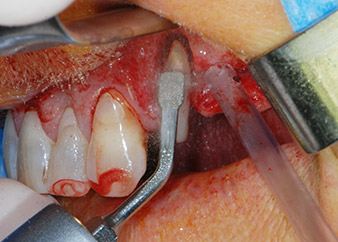

Un mes después, en el día de la intervención, el dolor y la inflamación se habían reducido al mínimo en la pieza 24, pero seguía habiendo una movilidad de clase II de Miller. Después de la apertura de los colgajos y de la limpieza del tejido infectado periapical y perirradicular, la extensión del defecto óseo quedó evidente (figuras 2 y 3).

la raíz bucal de la pieza 24 mostraba una pérdida total del hueso y de la fijación

Fig. 2 y 3: Después de abrir los colgajos, un mes después de realizar la revisión endodóntica y de iniciar la terapia periodontal en toda la boca, la raíz bucal de la pieza 24 mostraba una pérdida total del hueso y de la fijación.